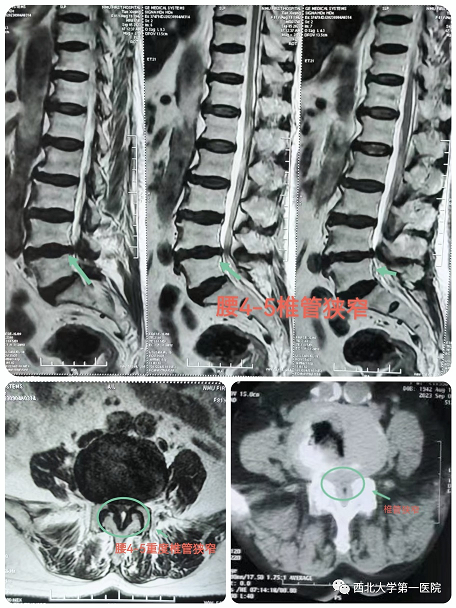

近日,21点策略指南站 骨科三病区(脊柱外科)团队成功为一位高龄(81岁)腰4-5椎管狭窄患者应用单孔分体式脊柱内镜技术(OSE技术)完成“内镜下腰椎管狭窄单侧入路、双侧减压、脊神经根粘连松解术”,取得了满意的临床效果。

患者田某某,女,81岁,有腰腿痛病史10余年,近期出现左下肢放射痛,不能长距离行走,辗转多家21点基本策略 保守治疗,效果不佳,行走困难,严重影响日常生活和休息,为求诊治,来21点策略指南站 骨科三病区。21点策略指南站 脊柱外科团队经过细致的体格检查及辅助检查,明确诊断:腰4-5椎管狭窄症。患者症状体征与检查结果相符,重度椎管狭窄,继续保守治疗可能没有效果。患者高龄,81岁,基础病较多,开放手术风险较高,患者及家属不能接受,与患者及家属充分沟通后,建议可以考虑微创椎管减压术,在取得患者家属的理解后,同意行微创手术治疗。

经过充分的术前讨论及围手术期多学科讨论评估后,决定采用目前最新脊柱内镜技术:OSE(Open Spine Endoscope)单孔脊柱内镜技术,行腰4-5椎管狭窄单侧入路、双侧减压、脊神经根粘连松解术。手术切口约2cm,术中出血10ml左右,由于不破坏关节突关节,不影响脊柱稳定性。术后第二天患者佩戴腰带下地活动,症状明显缓解,效果非常满意。

术中可见椎管减压彻底,神经根完全松解